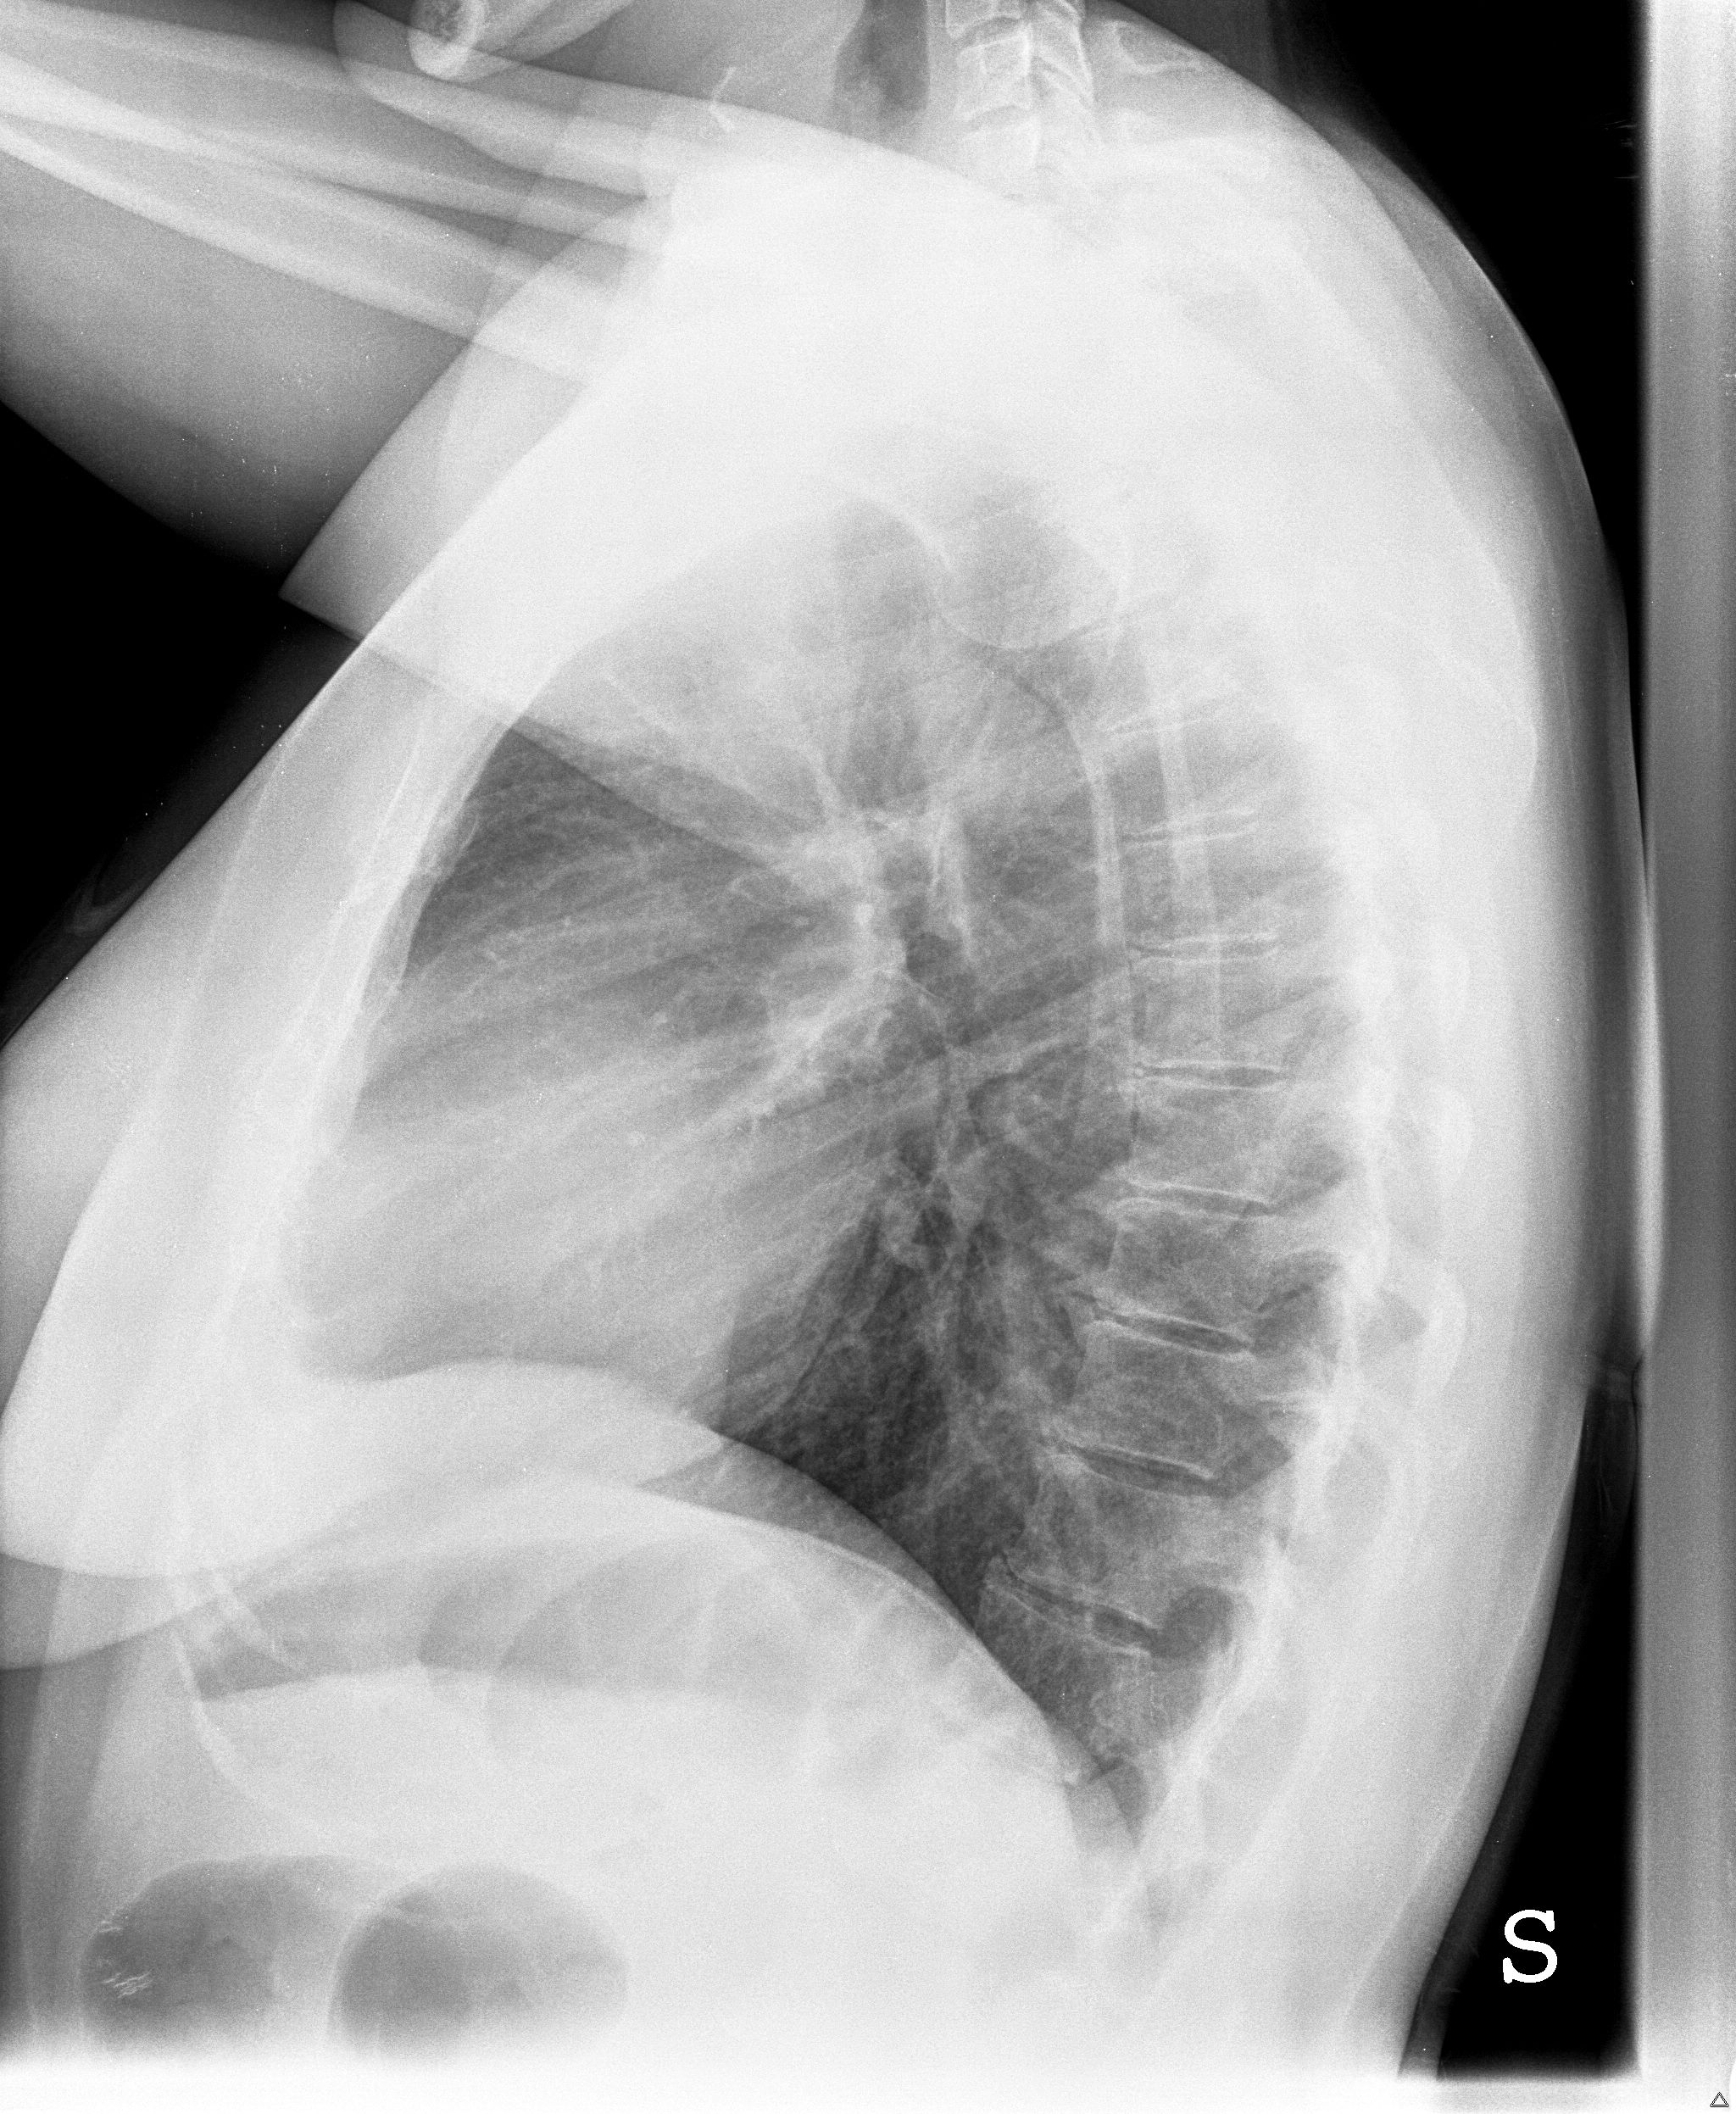

buongiorno dopo tutta una serie di esami effettuati nel corso di quest anno (ecocuore, gastroscopia, ecografia addome... tutti negativi) per capire l origine di questo mio fastidio ieri ho fatto i raggi al torace premetto che sono una fumatrice da 10 sigarette al di con un passato da fumo passivo non indifferente...vorrei capire se effettivamente ho qualcosa per cui preoccuparmi specifico che ho 39 anni

bis.jpg

[ 817.83 KiB | Osservato 4171 volte ]